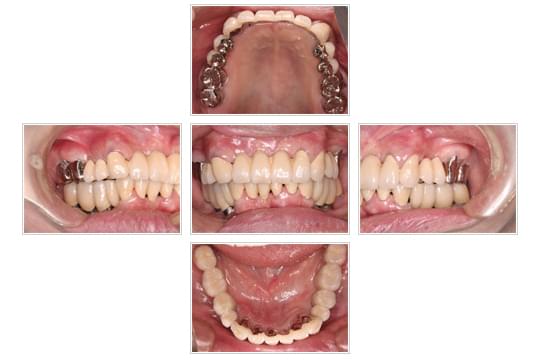

インプラントの治療例 (61歳)

咀嚼障害のご相談をいただきました。

全顎にわたる重度の歯周炎、動揺、排膿。

上下顎の歯周治療を行い、下顎臼歯インプラントによる全顎補綴。

インプラント埋入後

口腔内写真